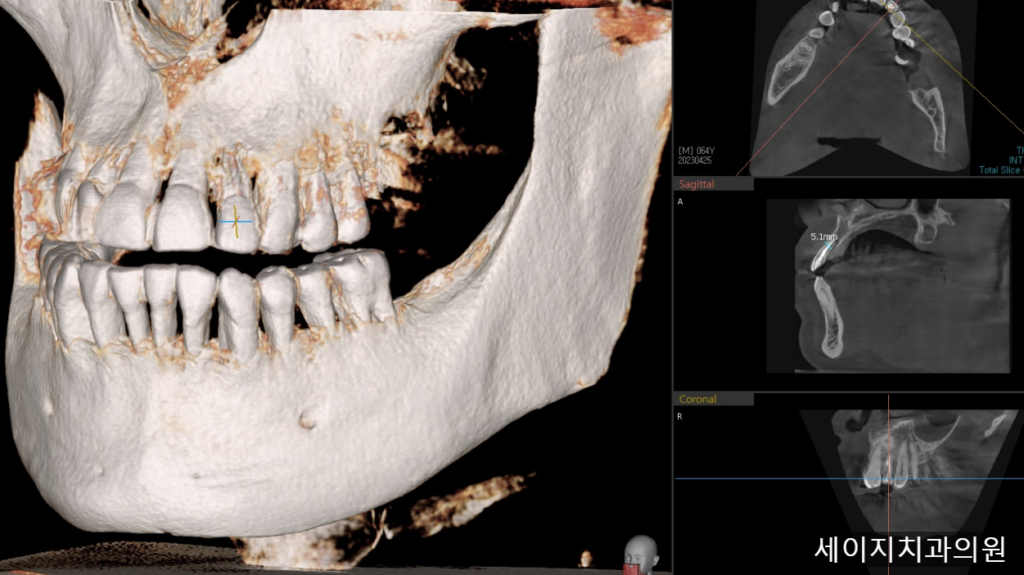

먼저 x-ray와 CT를 이용하여 정확한 뼈의 모습과 치아의 상태를 관찰하였습니다.

24. 05. 09

CT상으로는 입술에서 가까운 잇몸뼈의 흡수가 관찰되었습니다.

잇몸뼈의 소실이 크기에, 임플란트 진행시 심미적인 요소를 맞추기가 어려워 보였습니다. 때문에 환자분께 브릿지 치료도 하나의 옵션으로 권유드렸으나, 인접한 치아를 갈아내는 것에 대한 부담감이 크다고 이야기 해주셨습니다.